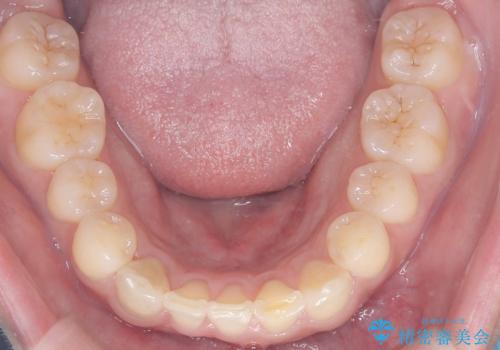

- 「歯の捻じれとがたつき」を主訴に来院された患者様です。

軽度な捻転と叢生だったため、インビザラインのモデレートで治療を行いわずか半年で治療を終える事が出来ました!

目立たないマウスピース矯正【インビザライン】を使用し、

わずか6ヵ月で歯並びがキレイに整いました!